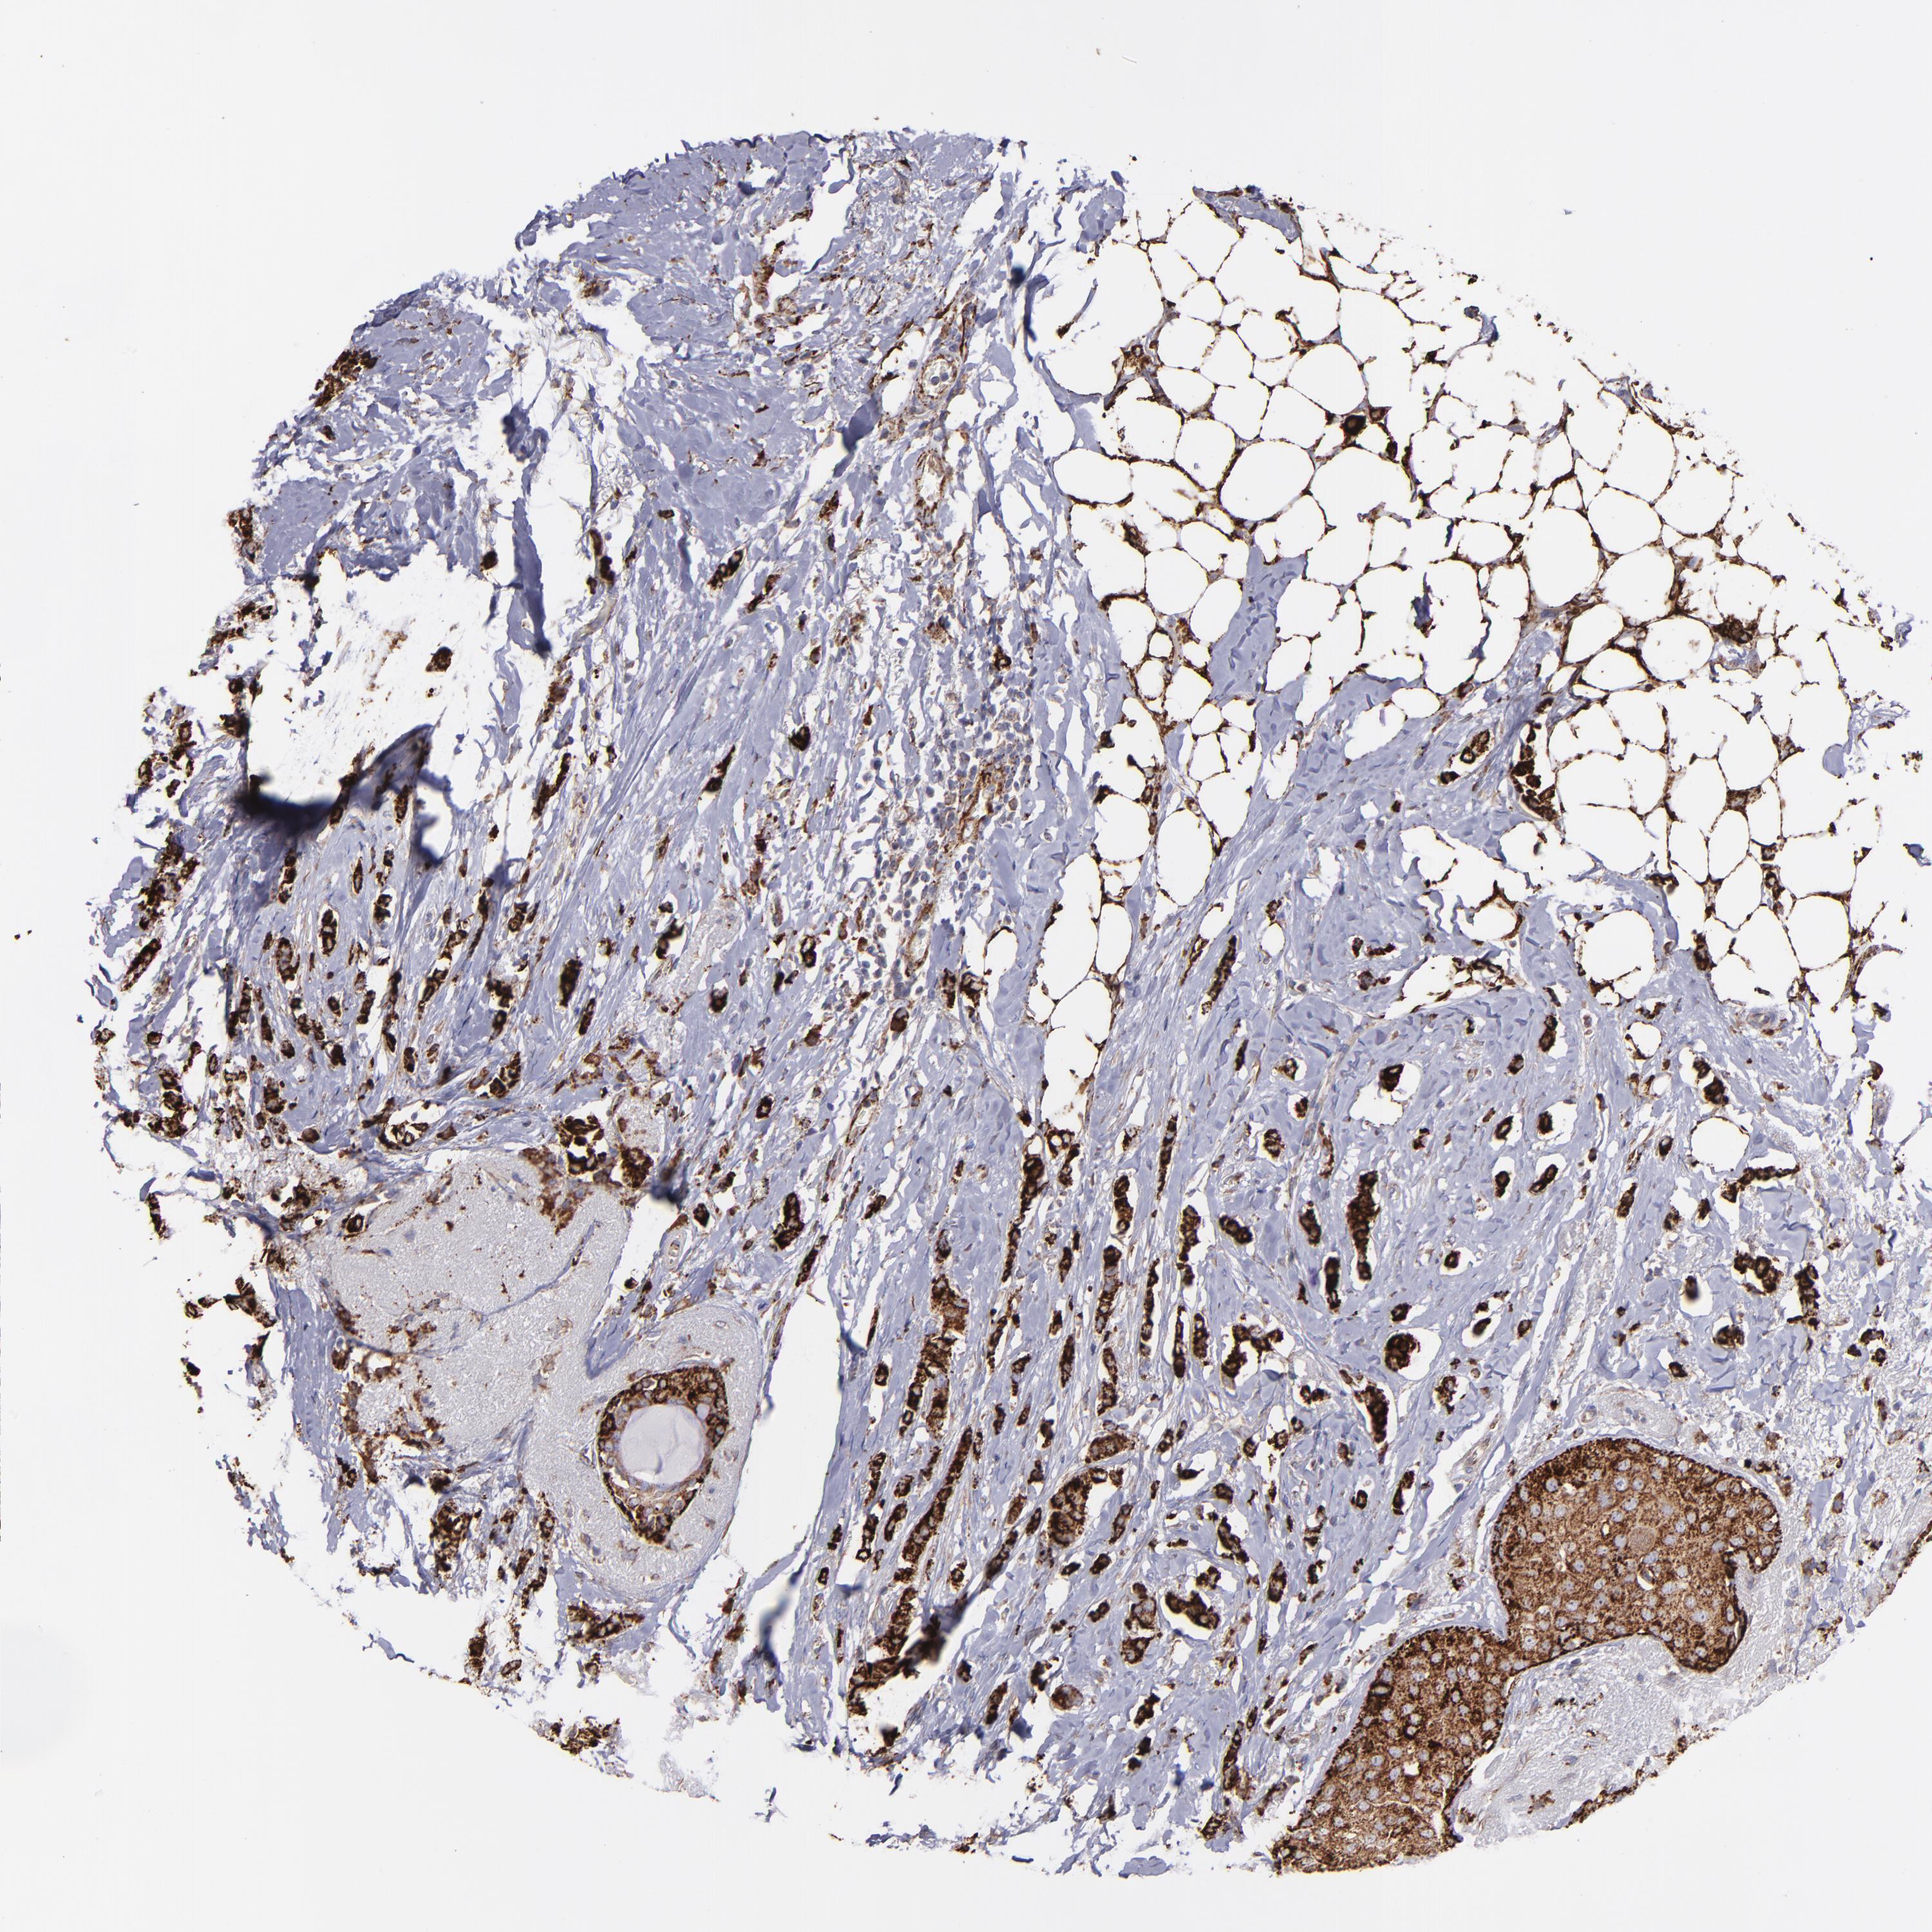

BRCA TCGA BRCA VALIDATION PROTEIN EXPRESSION